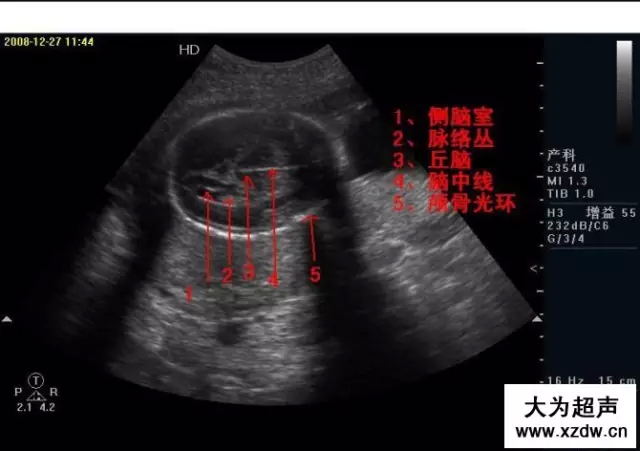

產科超聲正常圖片